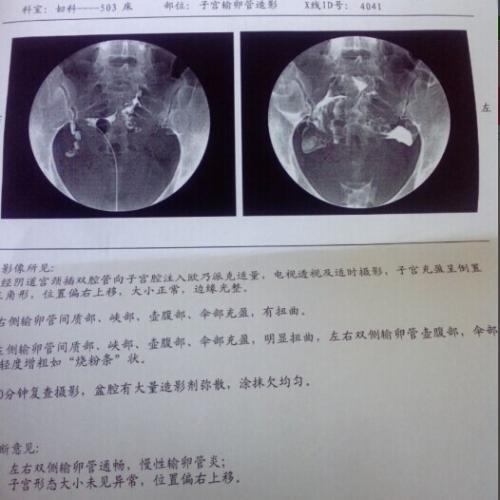

做子宫造影有哪些注意事项

做输卵管造影要多少钱?专家解读造影费用

做造影对身体的危害有哪些呢什么是子宫输卵管造影

什么情况下需要做输卵管造影

什么情况需要做输卵管造影

做造影有什么好处

跟大家分享一下我的输卵管造影经历

哪些人需要做输卵管造影?

姐妹们没有怀上,一定做个造影看看输卵管是否畅通.

4步讲解输卵管造影检查过程

输卵管造影不要随便做输卵管造影注意事项

输卵管造影2月19日做的造影2月20

备孕检查做输卵管造影疼吗影响输卵管造影疼痛的因素

你好,我做造影检查左侧输卵管梗阴,右侧

不孕,做了造影疑似宫腔粘连了帮忙看下

输卵管造影很疼吗?是怎么做的?

做输卵管造影前后,该需要注意什么?

做输卵管照影可以吃东西吗输卵管造影哪家强

做个输卵管造影能检查还能治疗?它有什么神奇之处?

输卵管造影检查注意事项

做输卵造影要做什么检查

超生输卵管造影费用图片合集